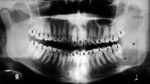

Three separate stages of dentition occur in humans (figure: stages of dentition). The earliest stage lasts up until approximately six years of age with the mouth containing 20 temporary deciduous teeth. During the second stage from ages 6 to 21, both the deciduous temporary teeth and the permanent teeth replacing them are present in the oral cavity. The timing of permanent tooth eruption varies according to the specific tooth. The third and final stage of dentition is observed in the adult. Commonly, this stage demonstrates 32 teeth, containing three molars, two premolars, one cuspid, and two incisors in each of the four quadrants in the mouth. Although 20 deciduous teeth and 32 permanent teeth is the most common presentation, patients may vary in their number of teeth. Adontia is the developmental absence of teeth, and may be total or partial. Extra teeth are a more common variant, particularly in the incisor region, and are referred to as supernumerary teeth.

Stages of dentition |

Mixed dentition in a child with permanent teeth plus retained primary teeth. The + marks developmental follicles for the third molar and the * marks permanent second molars. |